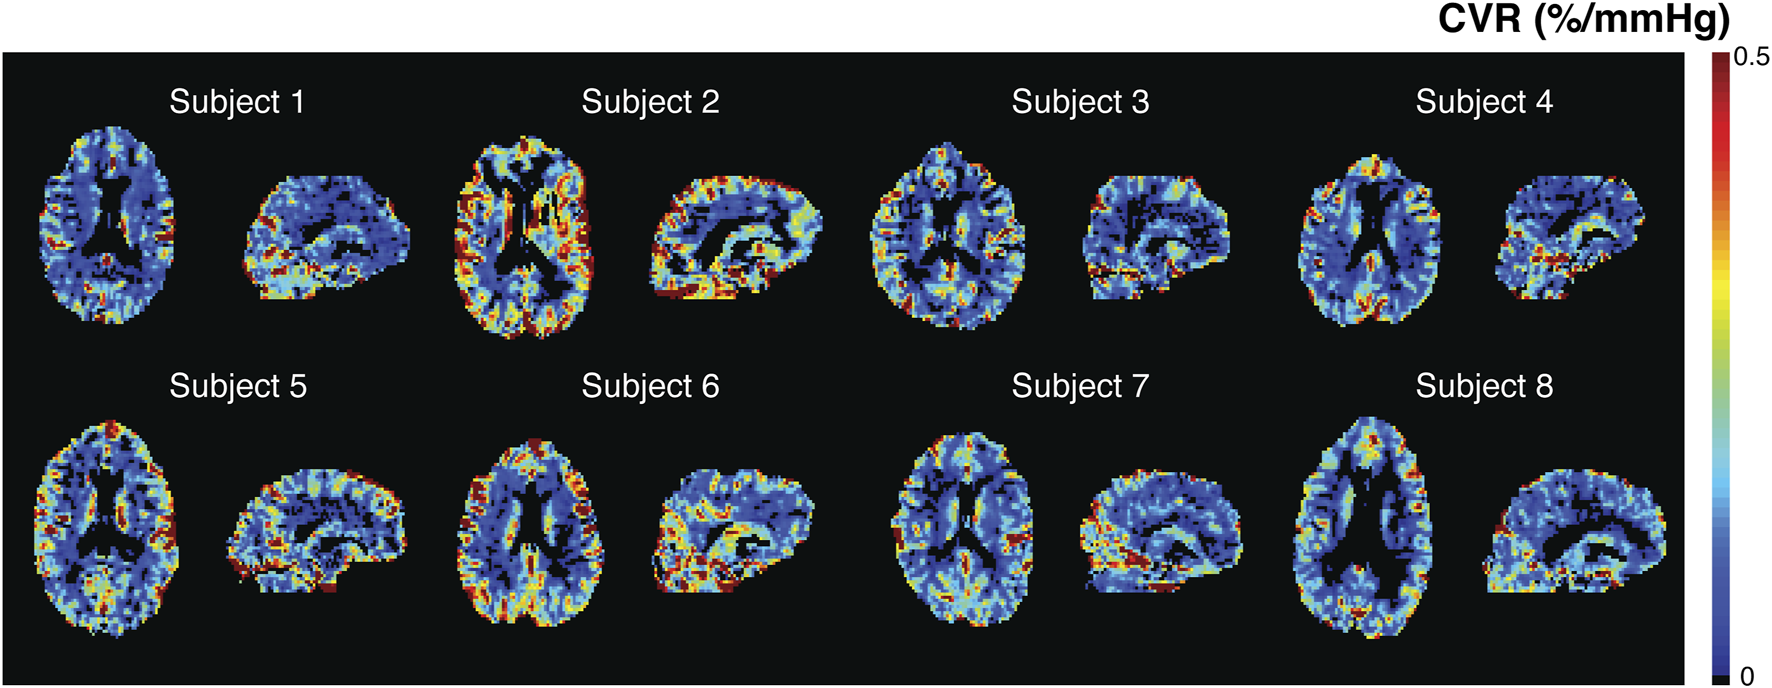

3.3 Cerebrovascular reactivity

Individual CVR maps are shown in Figure 4. Mean CVR was 0.24% ± 0.06%/mmHg in the cohort, significantly higher in the GM (0.28% ± 0.07%/mmHg) compared to the WM (0.13% ± 0.03%/mmHg, p<0.01). Spatial patterns of CVR maps are similar to CBF and CBV maps generated from the SineCO2 technique. Ratio maps between CBF and CVR (Supplementary Figure S5) demonstrated areas of negative CVR in the deep white matter areas as well as disproportionally higher ratio in the white matter compared to GM.

FIGURE 4

SineCO 2 CVR maps in individual subjects.